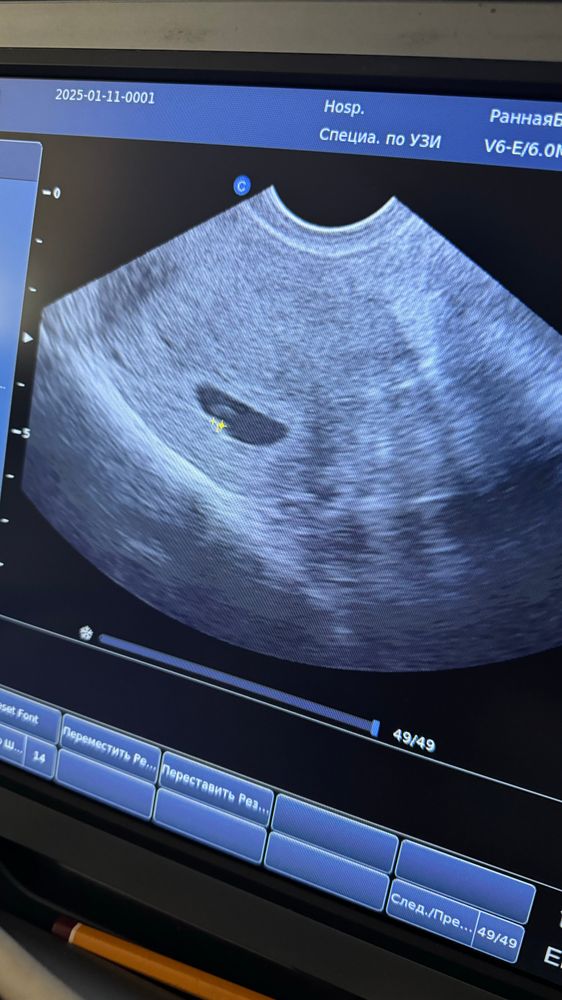

УЗИ в 6 недель

риск синдрома дауна Развитие эмбриона и плодного яйца